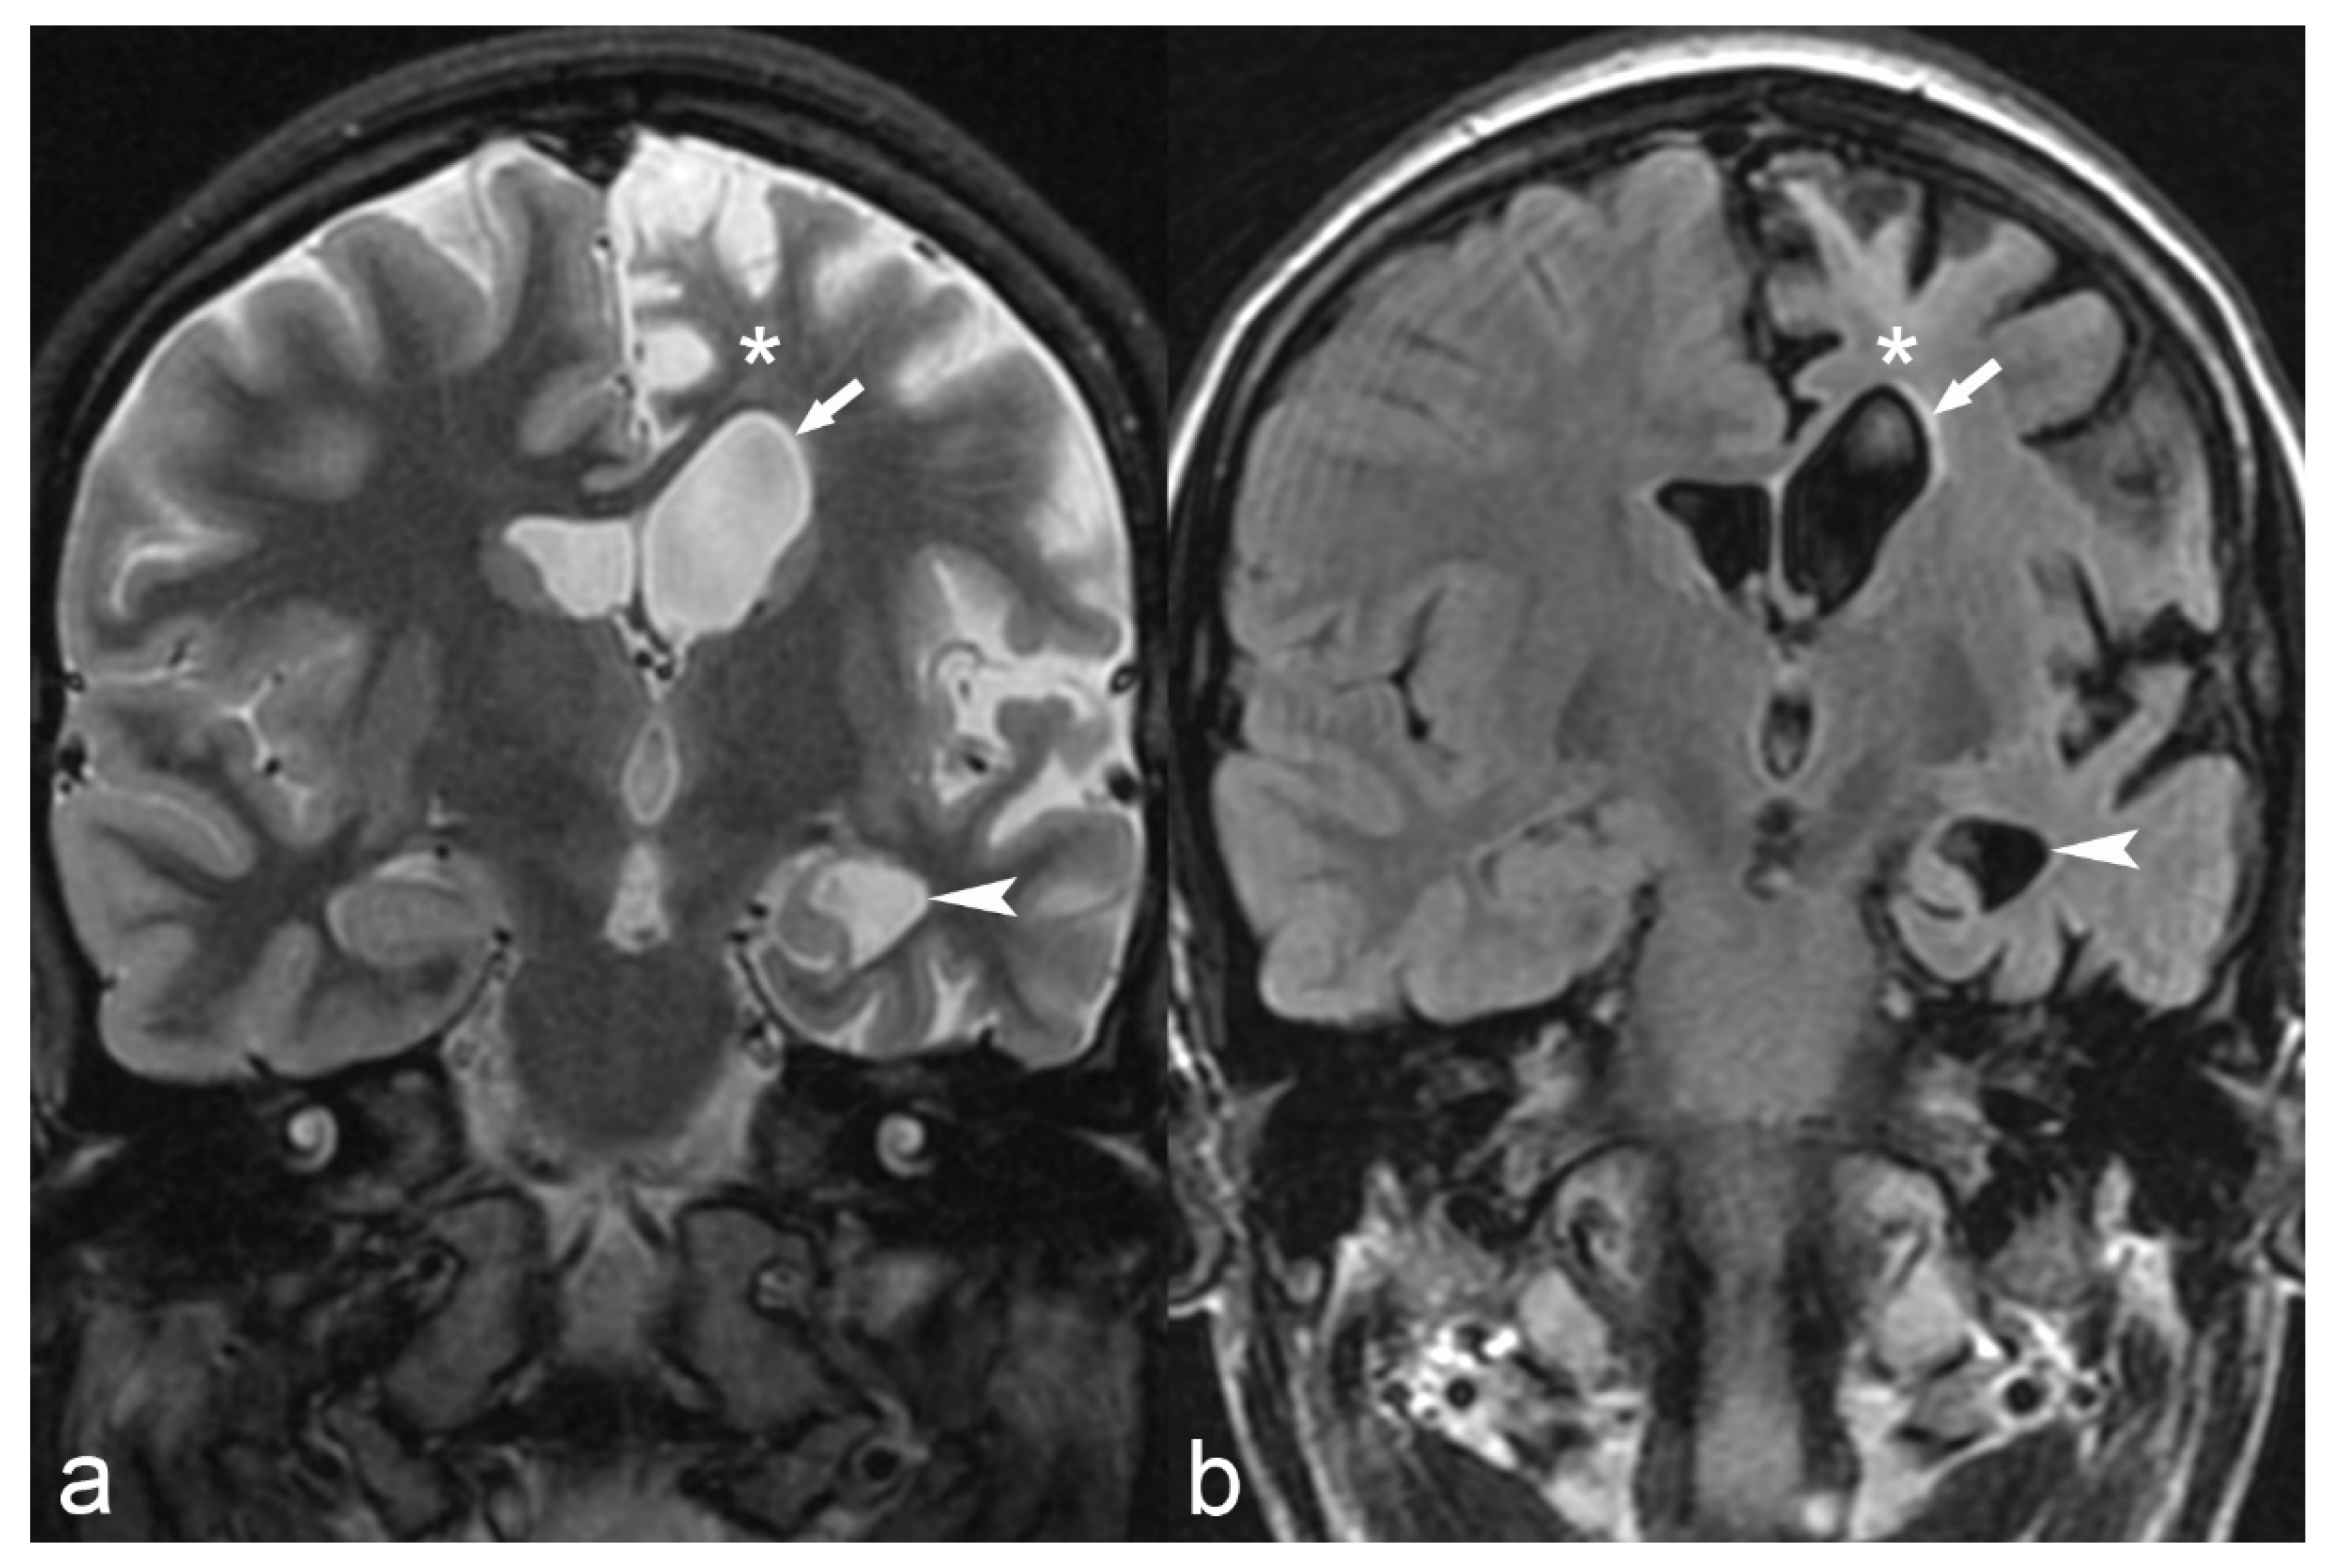

Figure 12.

18-year-old female with medically refractory epilepsy. Coronal T2 (a) and FLAIR (b) images show hemispherical parenchymal volume loss and cortical thinning (asterisk) on the left side with resultant ex vacuo dilatation of the frontal (arrow) and temporal horns (arrowhead) of the left lateral ventricle, consistent with Rasmussen’s encephalitis.